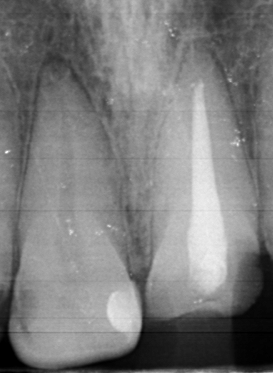

2323.jpg

Аноны, добрый вечер.

Посоветуйте пасту зубную после пломбирования и чистки от камня передних зубов.

Спасибо.

Аноним 06/08/25 Срд 05:38:29 #25 №1634925

Ска, весь рот в гное, будто бы стоматит, сходил к зубным феям - сказали все збс с корнями зубов и ни одного намёка на кариес где-либо, хотя начиналось всё будто бы флюс и самый пиздец около одного зуба, прописали онли антибиотики, но самое очко , что болезненность ещё и в области мягких тканей подбородка, который и отдает в этот самый пиздец при надавливании - даже будто бы второй подбородок чуть-чуть присутствует, температура и общая слабость, есть риск флегмоны? пиздец за шо(